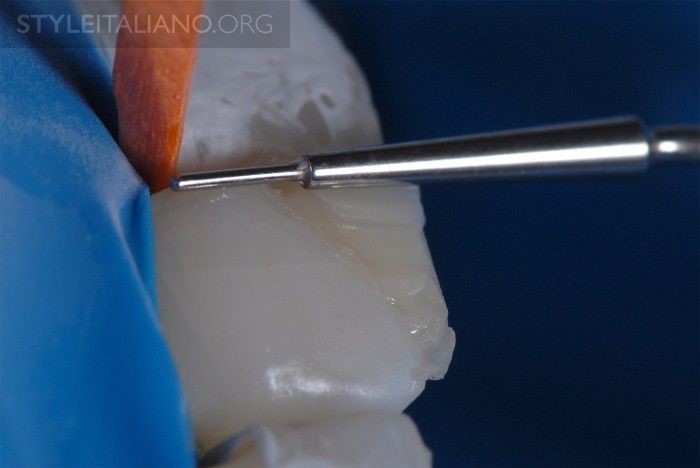

Hình 4. Tip 1: Vát men bằng mũi trụ thuôn dài và làm láng bờ viền. Mũi khoan kim cương 40 micron được dùng để làm láng lại đường viền lởm chởm do gãy, tạo ra vùng vát men trơn láng cách đường gãy từ 2mm trở lên. Điều này giúp làm láng đường viền và bo tròn góc cho các trụ men bị gãy.

Hình 5. Hình ảnh bờ viền sau khi được mài chỉnh bằng mũi kim cương. Khi mài vát men thì tốt nhất nên mài tạo dạng lượn sóng để khi ánh sáng phản chiếu vào miếng trám sẽ không đi theo đường thẳng.

Hình 6. Đài cao su đánh bóng sứ được sử dụng để làm nhẵn lại đường viền.

Hình 7. Sau đó, dùng đĩa Sof-Lex để đánh bóng lại và duy trì đường viền bevel.

Hình 8. Theo góc độ này, cho thấy đường viền bevel láng mịn và rõ ràng hơn.